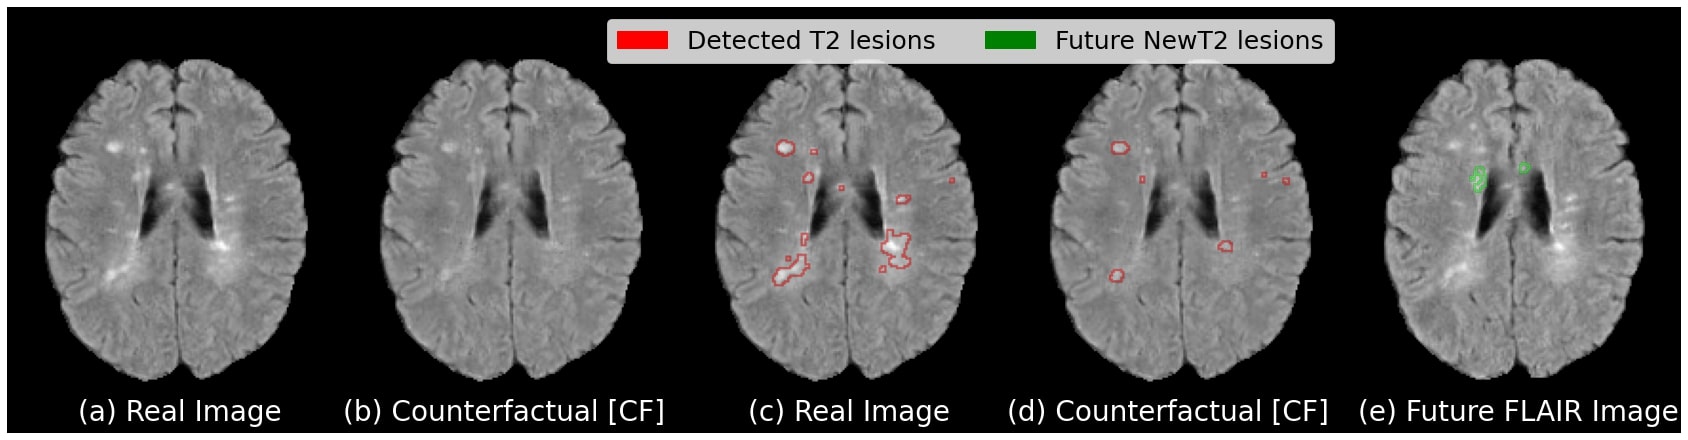

Subject-Specificity Figure 3 presents qualitative results for an illustrative test case. The counterfactual image in (b) shows a reduction in the number and size of the T2 lesions as compared to the real active image in (a). This can be seen by the T2 lesion segmentation maps produced by the pre-trained segmentation network, showing significantly less detected lesions in the counterfactual image (d) as compared to the real image (c). The counterfactual image maintains subject identity of the input scan with a similar overall appearance and a moderately reduced T2 lesion load. We also present the same subject’s image one year later in (e), where we can see the appearance of two new T2 lesions.

Personalized Marker Discovery Using a personalized approach to predictive image marker discovery, we would expect different individuals to have predictive markers in different locations, and potentially of a different type or appearance (e.g. in terms of magnitude of the perturbation). We would also expect these personalized markers to point to potentially novel processes beyond the aforementioned established population-level markers (T2 lesion volume and Gad count, in the case of MS). A qualitative analysis of different test cases demonstrating subject-level heterogeneity in the candidate image markers is shown in Figure 5. The candidate markers for subject (a) are found in a variety of locations including periventricular, deep white matter, and subcortical/juxtacortical, and cortical regions, while the candidate markers for subject (b) are localized to the periventricular region. In both cases, some perturbations occur in the region where future new T2 lesions will appear (or where existing T2 lesions will enlarge), indicating that the model has identified local predictive markers of future lesion activity. These changes are either in regions where there are T2 lesions in the real baseline image, or in regions where there are no lesions. This is in line with current understanding of how some lesions (enlarging lesions) enlarge slowly over time [5], and how non-lesional tissue called “diffusely abnormal white matter” can later transform into new/de novo T2 lesions [4]. Moreover, both cases also show candidate markers in brain regions distant to the area where NE-T2 will occur, indicating the discovery of global (rather than local) predictive markers of future activity. This is particularly noticeable in the cortex of subject (a), just anterior to the lateral ventricles. These global markers could represent a general predisposition to having more NE-T2 lesion activity (just as T2 lesion load in general is predictive of future lesion activity), but could also imply the importance of certain specific brain regions, tracts, or networks, in MS lesion development. These candidate markers are meant to form the basis of future scientific inquiry and can be the subject of dedicated validation studies.